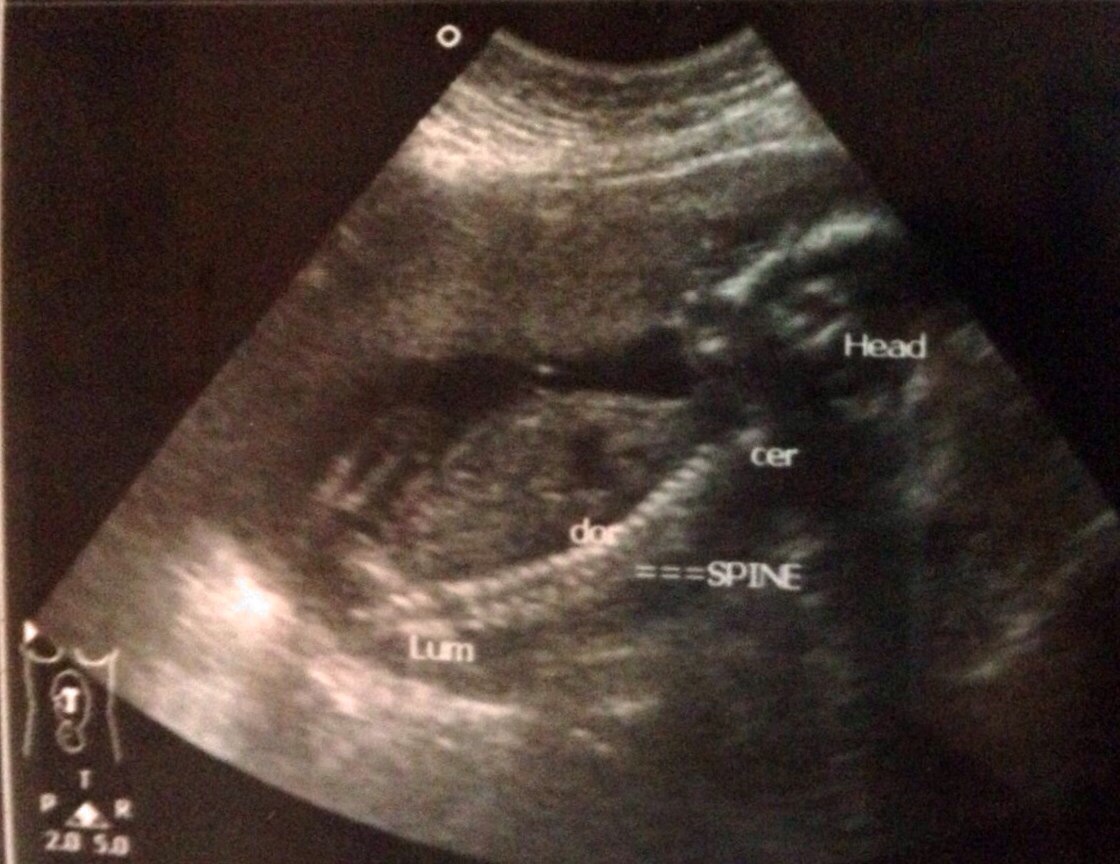

This 20+3 weeks scan. Pls guess the gender!Attachment 14247Attachment 14248Attachment 14249Attachment 14250

Maybe girl? You would really need a potty shot at this stage